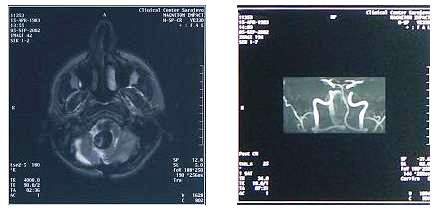

MRI je suverena za dijagnozu TIA ( gde je CT obično uredan ), te CVI u

predelu moždanog stabla i u zadnjoj lobanjskoj jami. (MRI sa krvarenjem

i izmenjenim velikim krvnim sudom u zadnjoj lobanjksoj jami-slika dole

levo)

Dijagnostika MRI

Promene na krvnim sudima se mogu evidentirati uz pomoć MRA

(magnetna angiografija - slika gore desno)